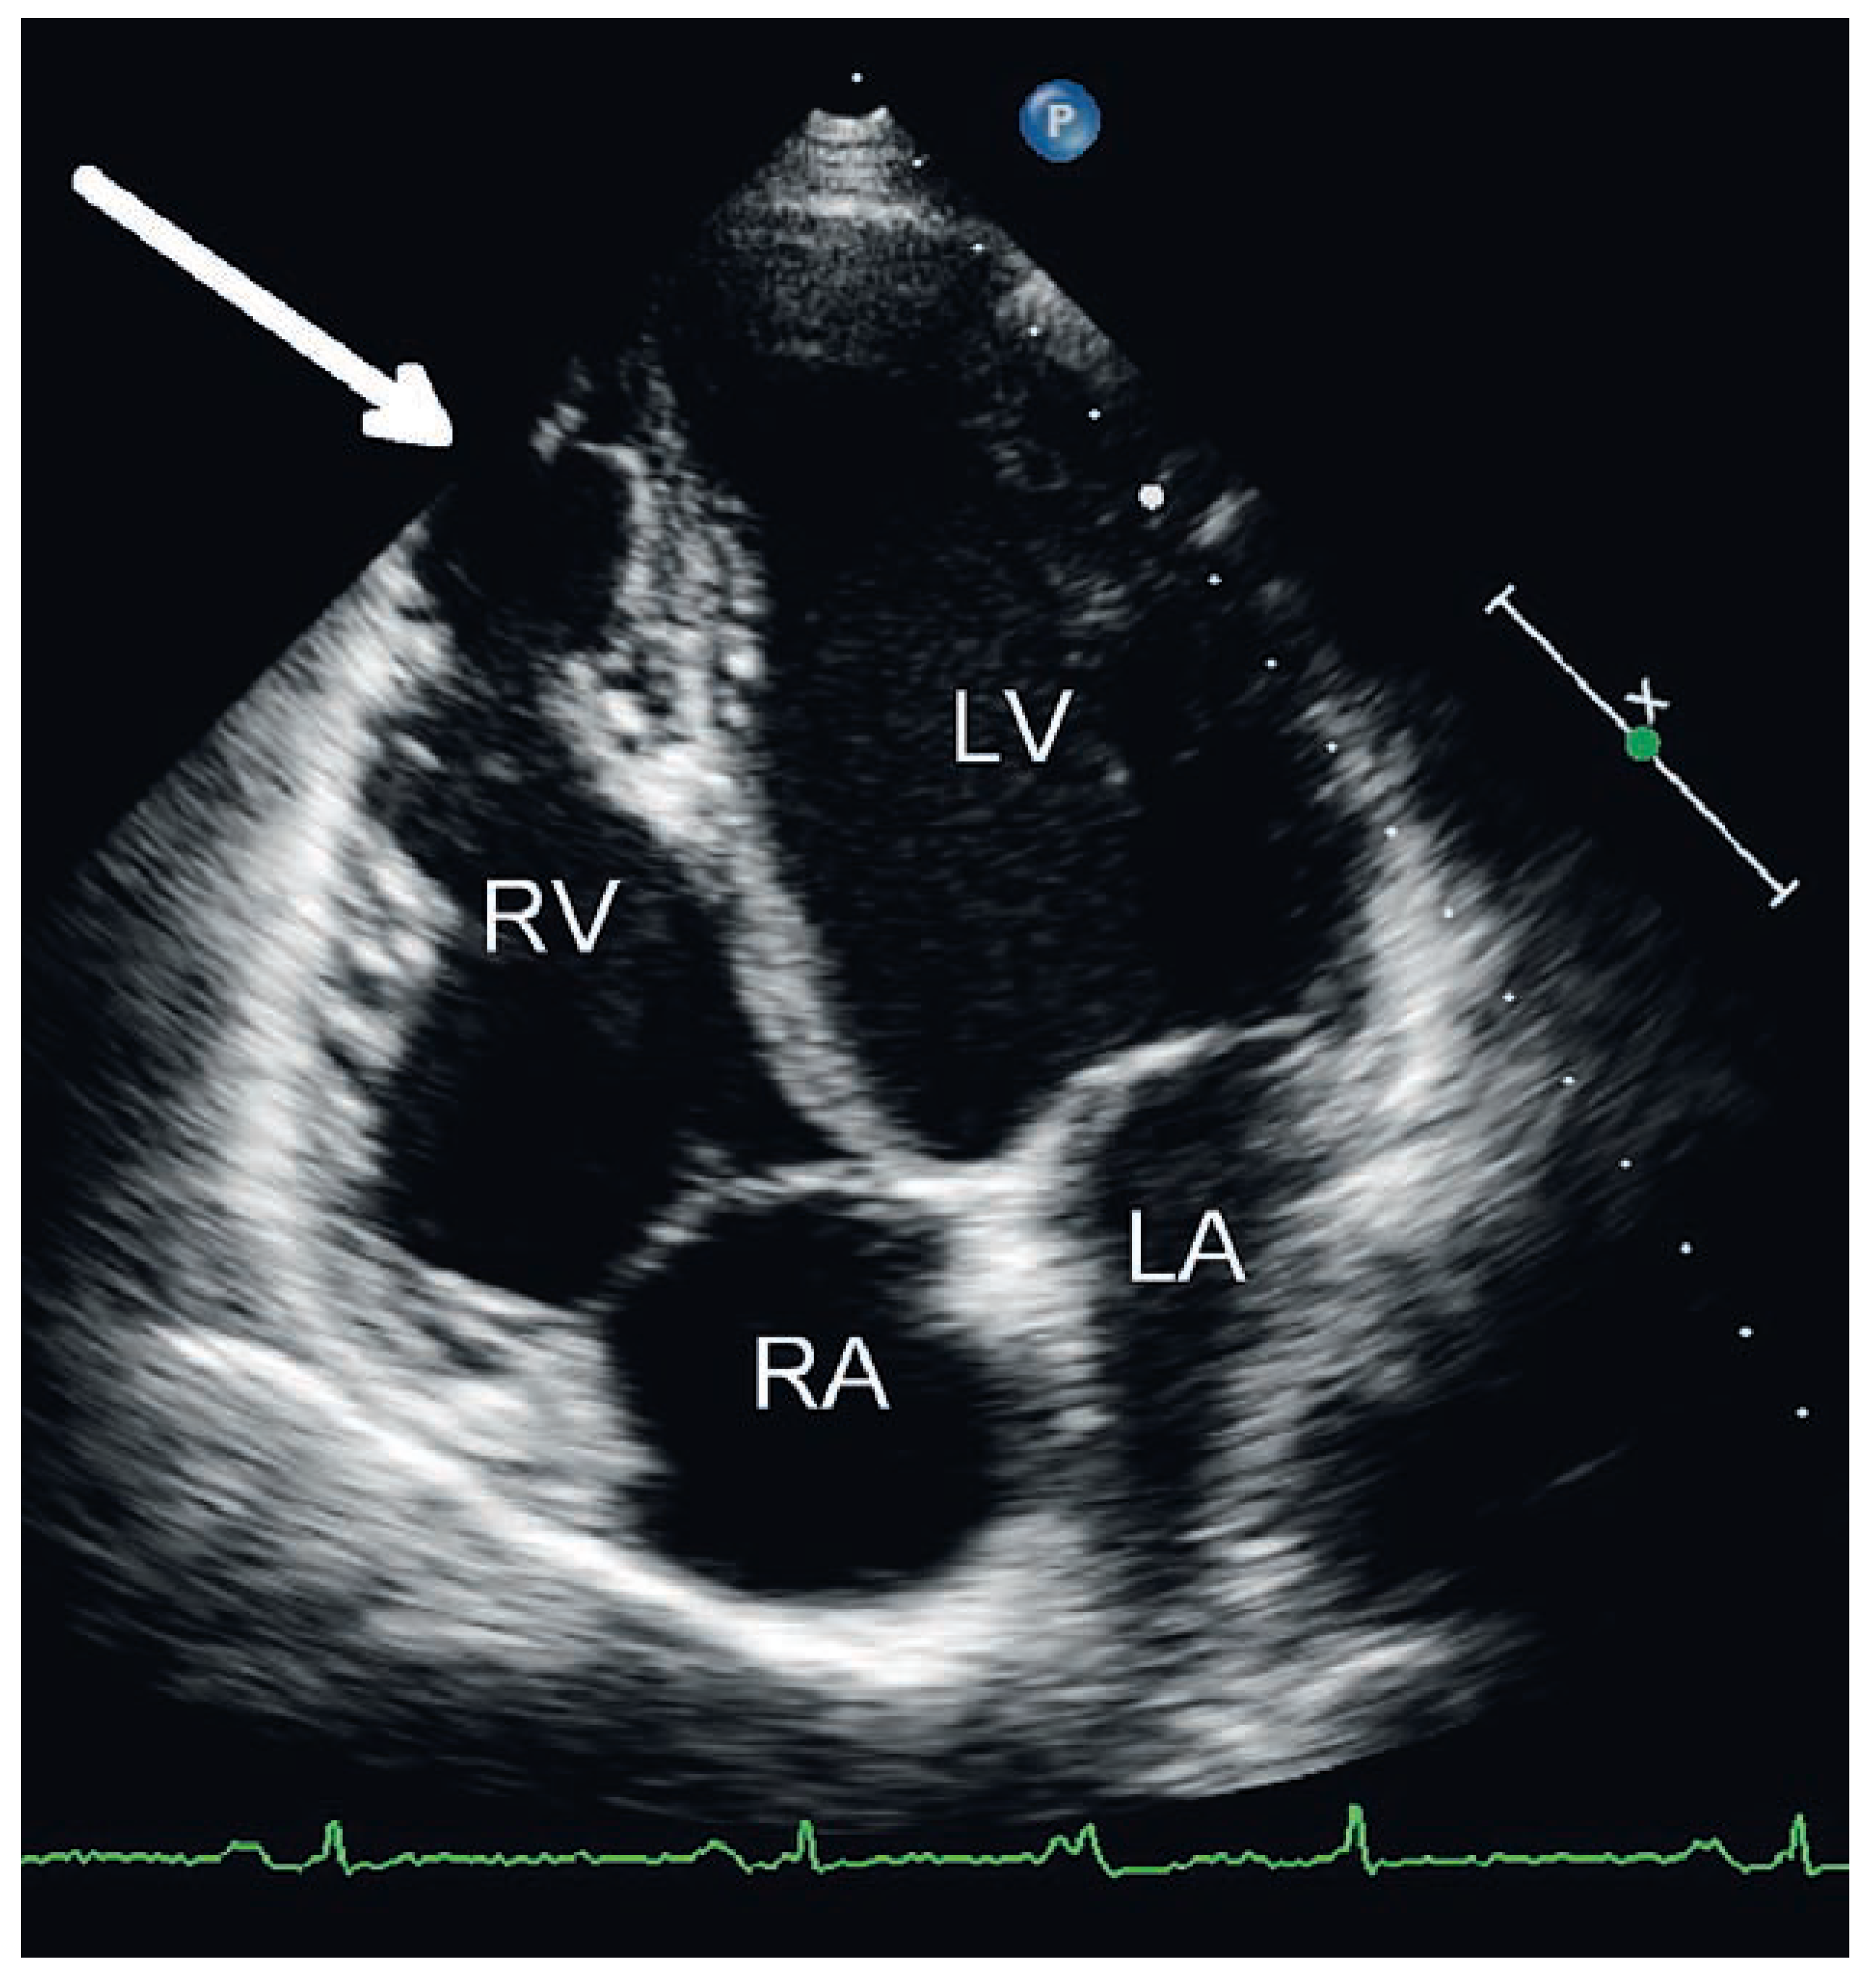

Ursprung der Extrasystolen

Fallbeschreibung

Diskussion